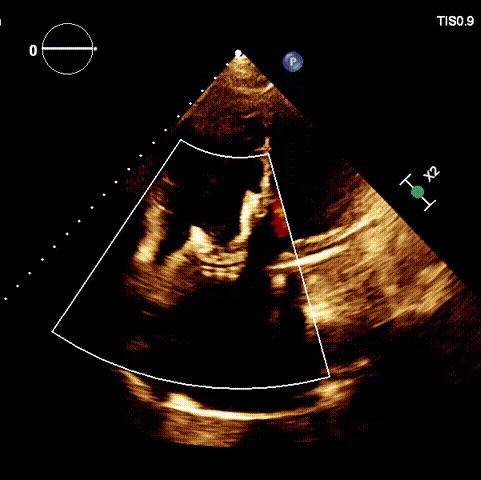

術后超聲

手術在全麻狀態下開展,海軍軍醫大學附屬長海醫院陸方林教授與廈門心血管病醫院王焱院長共同上臺,為患者進行手術。此次手術采用經右側頸靜脈入路的方式將輸送器送入患者心臟內,在TEE及DSA引導下調整輸送器頭端角度,使得輸送器與三尖瓣瓣環平面垂直。在輸送器進入右心室后釋放室間隔錨定裝置,而后釋放瓣葉夾持件(2個耳片結構)成垂直狀態。在TEE及DSA確定夾持件固定至三尖瓣葉根部且位于右室側后釋放人工瓣心房側盤片。隨后調整瓣膜同軸性以及室間隔錨定件位置(貼合室間隔),前推藏針管并固定,進而釋放室間隔錨定裝置,并再次確認瓣膜位置、穩定性及同軸性,合攏輸送鞘后撤出輸送器,完成LuX-Valve Plus人工三尖瓣瓣膜的植入。